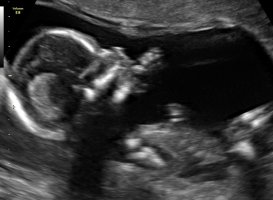

Jeg håper å kanskje få vite kjønn på neste UL, som kanskje er 31. oktober, men vi får se

Termin er satt til 30 april, men vi kan late som det er 1. mai vel, liker å henge her

Samtidig som jeg egentlig kunne valgt å ha ventet til fødsel. Men samboer klarer ikke vente. Så da håper vi at de ser noe kjønn på UL.skal da være 19+1.

Men tror ikke jeg klarer se nuben her dessverre